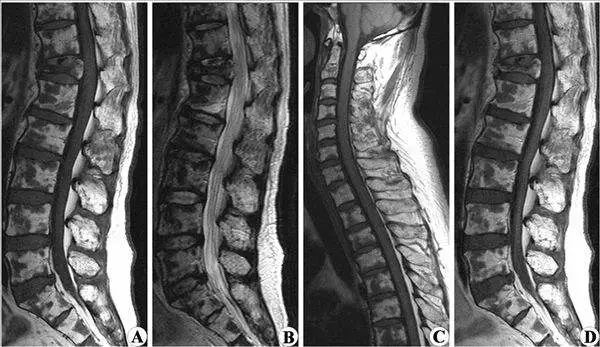

如果您有腰部急性外伤史,或者虽然没有急性外伤,但有渐进出现的腰痛伴下肢放射痛,麻痛超过膝关节以下,或者腰痛不明显甚至没有腰痛,而仅有超过膝关节的腿痛麻木的表现,再结合腰椎CT或MRI进一步明确腰椎间盘突出所压迫的神经根分布区域与临床出现的疼痛麻木部位相一致,基本可作出“腰椎间盘突出症”的初步诊断。

另一方面,可引起腰痛或腰腿痛的疾病有数十种,即使您CT、MRI提示有“腰椎间盘突出”,也有腰痛腿痛症状,临床医生还要根据您所表现的腰痛、腿痛是否与CT、MRI显示的“腰椎间盘突出”节段所压迫的神经根管辖的区段相符,来判断突出的椎间盘是否为“责任椎间盘”。如果相符“腰椎间盘突出症”的诊断才可成立,不相符,哪可能是其他原因引起的腰腿痛。

总之,CT、MRI表现出的“腰椎间盘突出”只是一种形态学上的改变,不一定会出现临床症状。这就好比是“乙肝两对半”阳性患者,如果肝功能完全正常,也无临床症状,就不能诊断为“乙型肝炎”,只能诊断为“乙肝携带者”的道理是一样的。所以我们大家一定要明确“腰椎间盘突出” ≠“腰椎间盘突出症”。绝不是CT、MRI报告是什么,临床诊断就是什么。